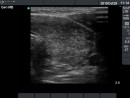

Follow-up examinations (rows from 1st to 8th):

2. Note the relation between volume, echogenicity, vascularization and hormone levels.